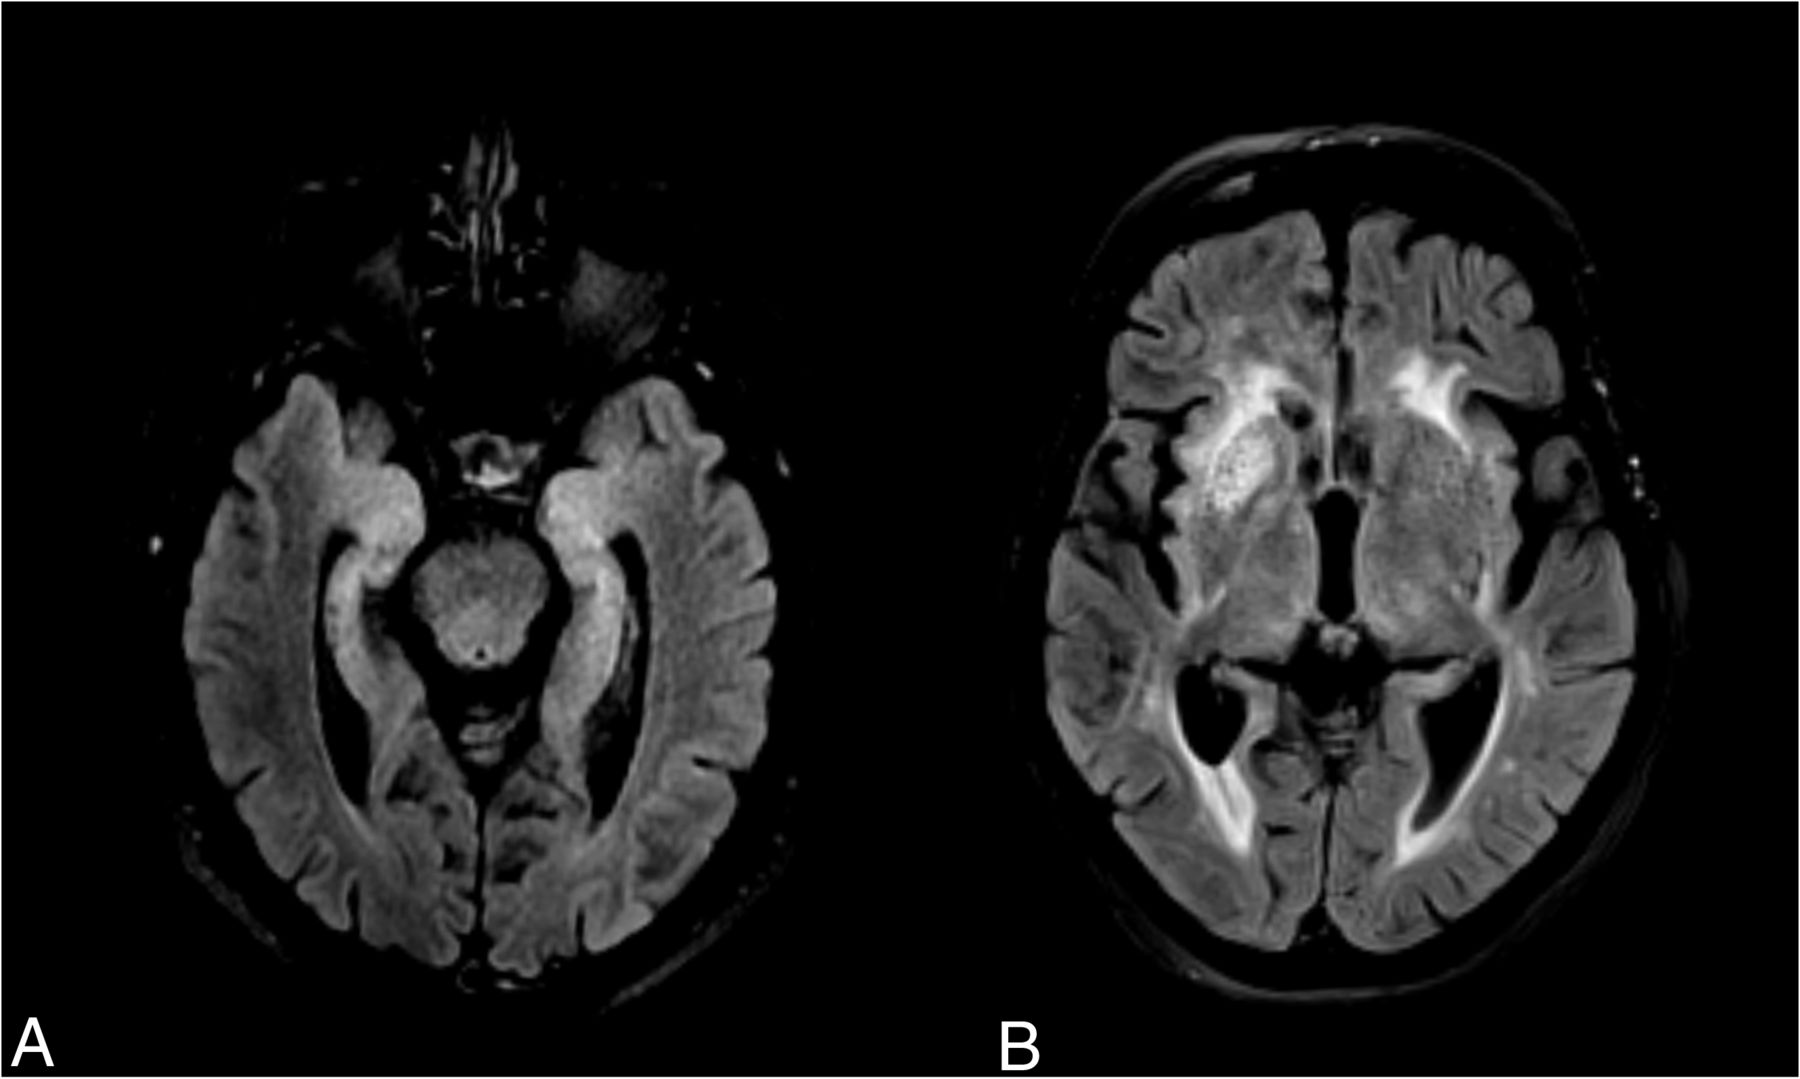

This disease typically presents with subacute cognitive impairment and epilepsy, but faciobrachial dystonic seizures (FBDS) are the most distinctive clinical feature. Although presenting across a wide variety of ages, it is thought to be most common in those older than 60 years of age.3 The clinical presentation thus leads to a vast differential diagnosis, in which clinical suspicion plays an important role.5,6 MR imaging is relevant in supporting the diagnosis of AIE and excluding alternative diagnoses. Characteristically, it involves medial temporal lobe (MTL) hyperintensities on T2 FLAIR sequences, which represent a criterion for a definite diagnosis of AIE when observed bilaterally (Fig 1A).7,8 This laterality issue is because in the absence of antibody confirmation, unilateral hippocampal/MTL abnormalities have a wider radiologic differential diagnosis.7,9 The main diagnostic considerations in this imaging presentation include seizure-related MR imaging abnormalities;10 viral encephalitis, particularly herpes simplex virus 1 and 2 and human herpesvirus 6;11 neurosyphilis;12 Whipple disease,13 temporal lobe glioma,14 and acute posterior circulation ischemic infarction.15

Illustrative examples of signal abnormalities in 2 cases of confirmed anti-LGI1 encephalitis, one with medial temporal lobe T2-FLAIR hyperintensities (A) and another with right BG T2-FLAIR hyperintensity (B).

However, not all cases of anti-LGI1 encephalitis present with MTL abnormalities at the time of MR imaging. MR imaging can also be unremarkable or show basal ganglia (BG) involvement (Fig 1B).16 Moreover, given the relatively recent description of the wide range of antibodies causing AIE, MR imaging findings are not yet thoroughly described for each antibody group.8,17 It is, therefore, important to provide prevalence estimates of MR imaging abnormalities in the literature for each type of antibody-mediated encephalitis. Indeed, given the wide clinical and brain imaging differential diagnoses involved in these cases, detailing the prevalence of specific patterns of abnormal findings on MR imaging for each encephalitis might aid the radiologist in providing a narrower differential while waiting for laboratory results.

Notably, BG signal abnormalities, encompassing both T2 and T1 hyperintensities and T1 hypointensities, were reported in around 10% of patients (Fig 5). The available number of studies providing information regarding the BG was substantially smaller than that for the MTL. However, these changes can be the sole signal alteration observed on MR imaging and might be unilateral16 (Fig 1B), suggesting that this brain region deserves detailed attention when suspecting AIE. In fact, LGI1 expression is high in the BG in humans (Fig 6B), and [18F] fluorodeoxyglucose PET studies have repeatedly shown metabolic alterations in these regions.27,39,41 Most important, these lesions can present with diffusion restriction,16 the cause of which is unknown. Ischemic infarction is thus an important differential diagnosis, and attention to clinical presentation is crucial.